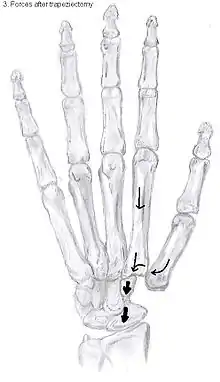

Trapeziectomy

During trapeziectomy,[30] the trapezium bone is removed without any further surgical adjustments.The trapezium bone is removed through an approximately three centimeter long incision along the lateral side of the thumb. To preserve surrounding structures, the trapezium bone is removed "by splitting" it into pieces.

An empty gap is left by the trapeziectomy and the wound is closed with sutures. Despite this gap, no significant changes in function of the thumb are reported.[27] After the surgery, the thumb will be immobilized with a cast.

Trapeziectomy with Tendon Interposition

Some physicians still believe that it is better to fill the gap left by the trapeziectomy. They assume that filling the gap with a part of a tendon is preferable in terms of function, stability and position of the thumb. This is based on the assumption that interposition can help maintain the space between the metacarpal and the scaphoid, which will improve comfort and capability. Neither of these assumptions is supported by experimental evidence.

Trapeziectomy with Ligament Reconstruction

Another technique is used to reconstruct the volar beak ligament after trapeziectomy. The rationale is that ligament reconstruction(LR) helps maintain the gap between the metacarpal and the scaphoid, and that a larger gap is associated with greater comfort and capability.[32] Again these possibilities are not supported by experimental evidence.

Trapeziectomy with LRTI

Some physicians believe that combining LR with TI will help maintain gap between the metacarpal and the scaphoid.[33] And that doing so will improve comfort and capability. Keep in mind that these aspects of the rationale are not supported by experimental evidence. The evidence suggests that all of these procedures have comparable long-term results.